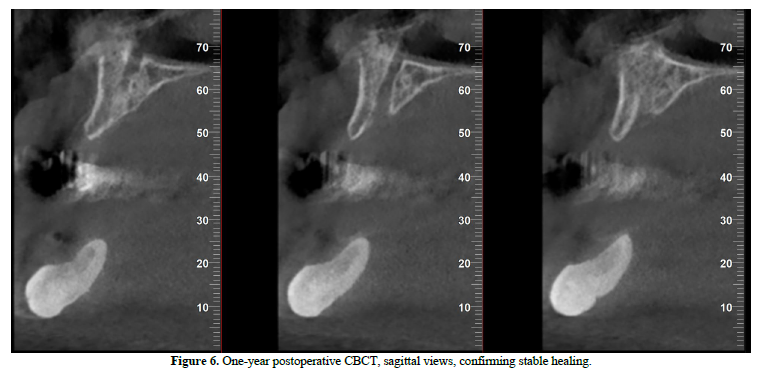

At the one‑year follow‑up, intraoral examination showed complete mucosal healing (Figure 11). CBCT acquired at the same visit—axial, sagittal, and frontal views plus three‑dimensional reconstruction—demonstrated stable bone remodeling of the anterior mandible (Figures 5–8). A one-year postoperative panoramic radiograph also confirmed preserved mandibular continuity, absence of recurrent pathology, and satisfactory bone healing (Figure 12).